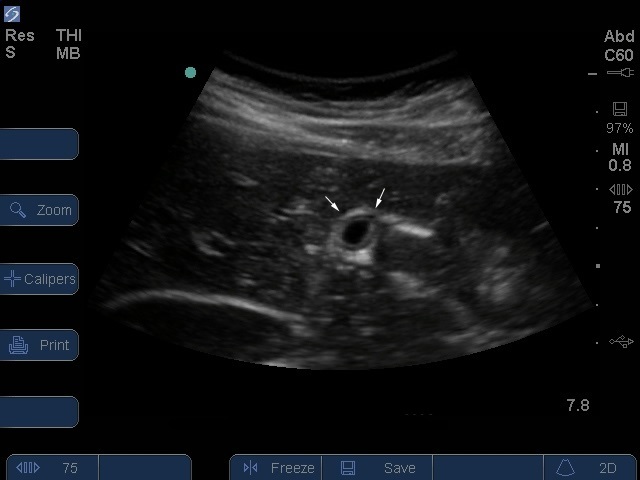

Postprandial transverse de la vésicule biliaire